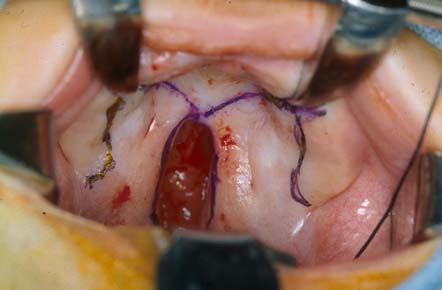

La palatoplastia se puede realizar como una etapa de reparación de 1 o (en raras ocasiones) 2 etapas y se realiza mediante la generación de colgajos de tejido bucal desde el paladar y la rotación de estos colgajos palatinos para permitir un cierre de 3 capas (mucosa bucal, músculos del paladar blando y membrana nasal).

• La técnica de 2 colgajos es el pilar de la palatoplastia unilateral, con la incorporación de una disección del vómer (componente óseo del tabique nasal que se encuentra debajo de la placa perpendicular del etmoides y detrás del cartílago cuadrangular del tabique nasal anterior) en la palatoplastia bilateral. Un paladar hendido secundario más pequeño se cierra mediante una plastia de von Langenbeck, de 3 colgajos (pushback, Veau-Wardill-Kilner) o de doble Z opuesta de Furlow, según la preferencia del cirujano.[56][57][58][Figure caption and citation for the preceding image starts]: Reparación de paladar hendido que muestra un diseño de von LangenbackDe: Senders CW, Sykes JM. Paladar hendido. En: Smith JD, Bumsted RM, eds. Pediatric facial plastic and reconstructive surgery. New York, NY: Raven Press; 1993:162 [Citation ends].com.bmj.content.model.Caption@401d059a[Figure caption and citation for the preceding image starts]: Reparación de paladar hendido que muestra un diseño de palatoplastia de 3 colgajosDe: Senders CW, Sykes JM. Paladar hendido. En: Smith JD, Bumsted RM, eds. Pediatric facial plastic and reconstructive surgery. New York, NY: Raven Press; 1993:162 [Citation ends].com.bmj.content.model.Caption@598ddeff[Figure caption and citation for the preceding image starts]: Reparación de labio hendido que muestra un diseño de palatoplastia en doble Z inversa de FurlowDe: Senders CW, Sykes JM. Paladar hendido. En: Smith JD, Bumsted RM, eds. Pediatric facial plastic and reconstructive surgery. New York, NY: Raven Press; 1993:162 [Citation ends].com.bmj.content.model.Caption@55e72497

• La técnica de 2 colgajos se aplica de la siguiente manera: una vez que se marca el paladar con el diseño elegido, se corta el colgajo de mucosa bucal en dirección descendente hacia los huesos del paladar y se eleva en un plano subperióstico. Los vasos más grandes del paladar se preservan y los colgajos se mueven para permitir que las membranas bucales entren en contacto entre sí internamente. Los músculos del paladar blando (tensor del velo palatino y elevador del velo palatino) se diseccionan para permitir un cierre sin tensión después de la incisión y el cierre de las membranas nasales. Para el cierre, se utilizan suturas reabsorbibles y se minimiza la tensión en las líneas de sutura mediante la movilización adecuada de los colgajos.[Figure caption and citation for the preceding image starts]: Reparación de paladar hendido que muestra un diseño de palatoplastia de 2 colgajosDe: Senders CW, Sykes JM. Paladar hendido. En: Smith JD, Bumsted RM, eds. Pediatric facial plastic and reconstructive surgery. New York, NY: Raven Press; 1993:162 [Citation ends].com.bmj.content.model.Caption@4abcdf6b